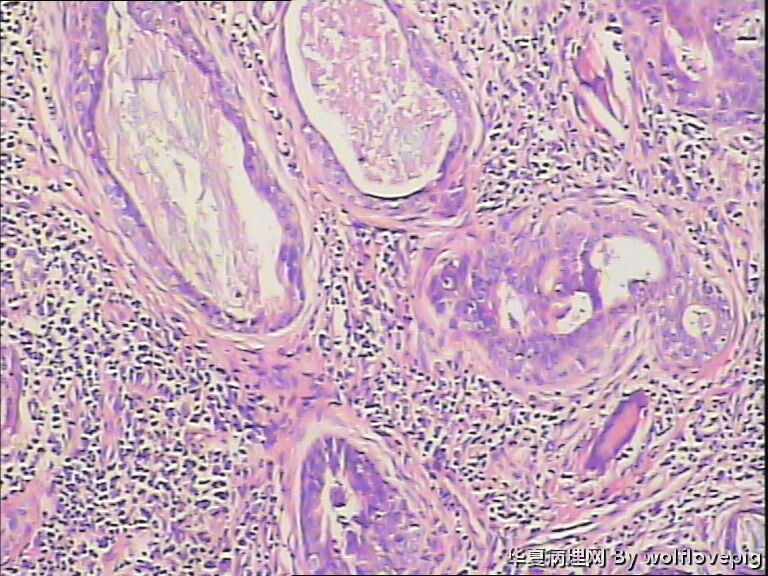

男,38y,腹部皮肤硬节20年。灰白不整形带皮组织一块:3.0*1.5*1.4cm,皮肤表面可见多个小结节样隆起。

图4